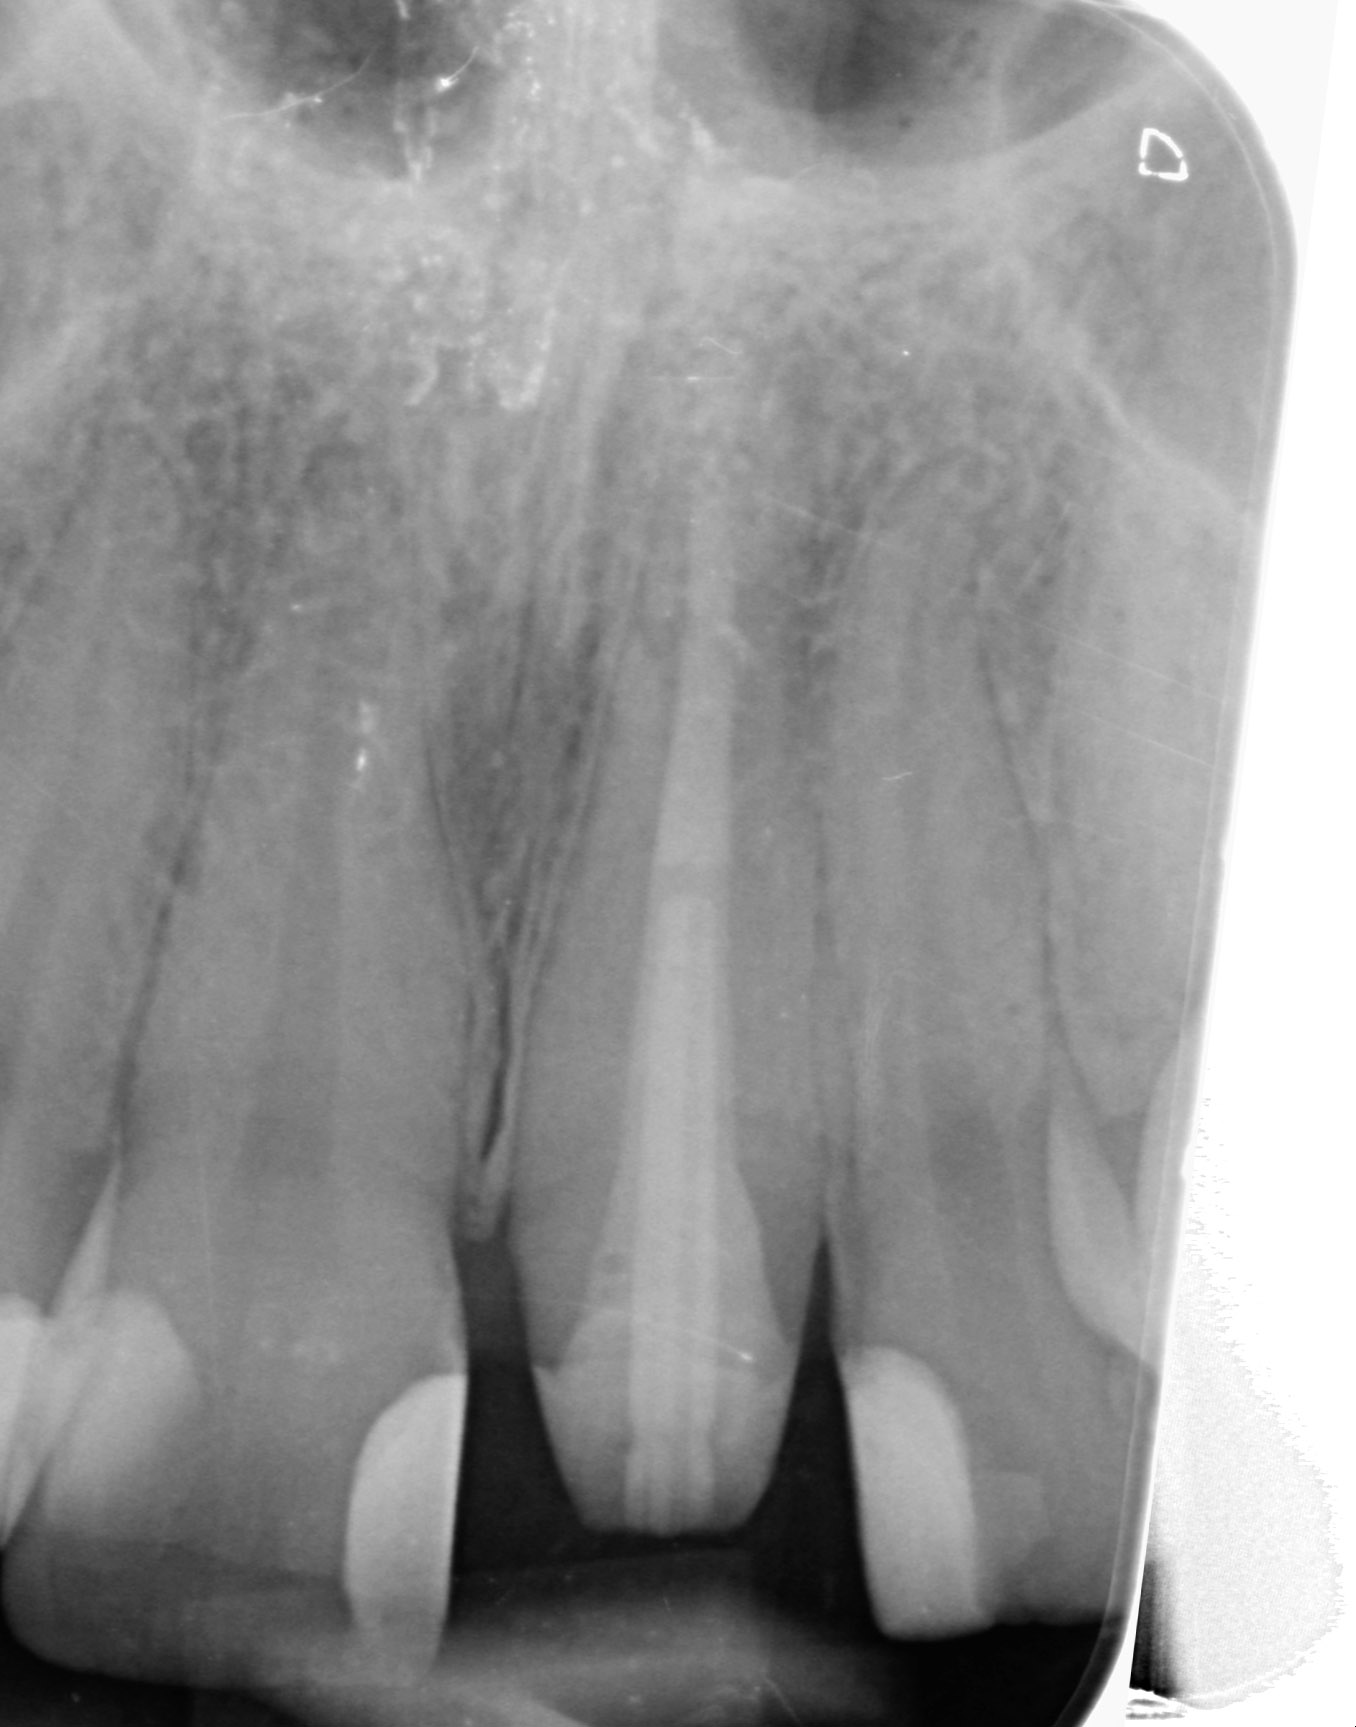

Mikroskopická endodoncie

Komplikovaný kanálkový systém nemusí znamenat kompromis. Rádi za Vás takové případy ošetříme, či provedeme reendodoncii.